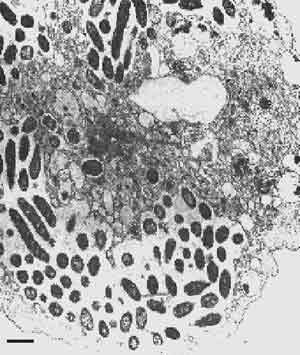

Рис. 2. Цитомегаловирусное повреждение сетчатки глаза человека при СПИДе. В большинстве случаев цитомегаловирусной инфекции отмечается бессимптомное вирусоносительство. Однако при СПИДе патогенные свойства вируса проявляются разнообразными поражениями, невозможными в иммунокомпетентном организме. Цитомегаловирус, как и ВИЧ, способен подавлять клеточный иммунитет хозяина. Поэтому действие обоих вирусов на иммунную систему интегрировано. Видимо ближе к истине будут О.В. Бухарин, В.Ю. Литвин (1997), считающие, что патогенность не всегда удается адекватно оценить в «чистом виде», так как она может быть интегрированным результатом действия нескольких сочленов паразитоценоза хозяина. На рисунке видны участки отмершей ткани (светлые) и облитерация кровеносных сосудов (темные участки). Черная область — отслоившиеся участки [Милз Д., Мазур Г., 1990]